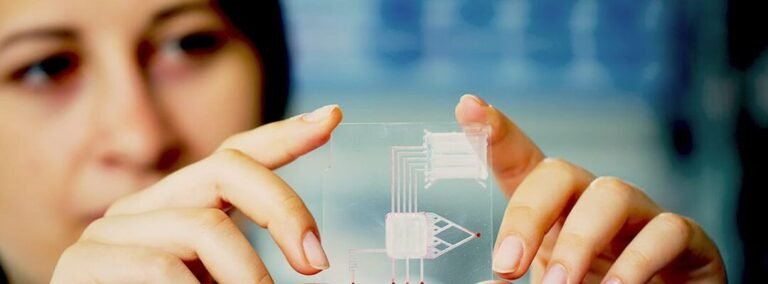

La bioingeniería de tejido hepático para pruebas de toxicidad representa un avance clave en la investigación médica...